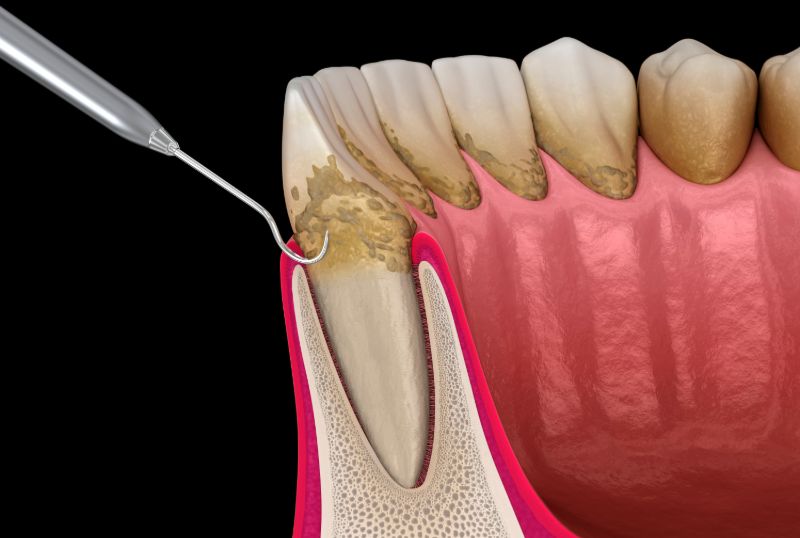

歯と歯ぐきのすきま(歯周ポケット)から細菌が侵入し、歯肉に炎症を引き起こしたり、歯を支える骨(歯槽骨)などが溶けたりする病気です。

歯を失う80%以上の原因は歯周病もしくはむし歯によるものといわれています。

歯肉の辺縁が炎症を起こし赤くなったり、腫れたりしますが、むし歯と異なり痛みが出ないことが多く、気づかないうちに進行します。

歯肉からの出血の後、歯が自然に抜け落ちるほど重症になることもあります。

歯周病は、とくに初期の段階では自覚症状がないため、歯科での検査を受けないと正確な診断を行うことはできません。

「歯ぐきの腫れ」「歯ぐきからの出血」「歯のぐらつき」などは歯周病のサインともいえますので、このような症状がありましたらお気軽にご相談ください。

予防の基本は歯垢がつかないようにすることです。

歯垢は取り除かなければ硬くなり、歯石となり、歯の表面に強固に付着します。

この歯石の中や周囲に細菌が入り込み、歯周病を進行させる毒素を出し続けていきます。

歯周病の予防では、毎日の歯みがきを欠かさずに行い、定期的に歯石を除去することが有効的です。

歯周病になった場合には、歯科で専門的なクリーニングや咬み合わせの調整などが必要となります。